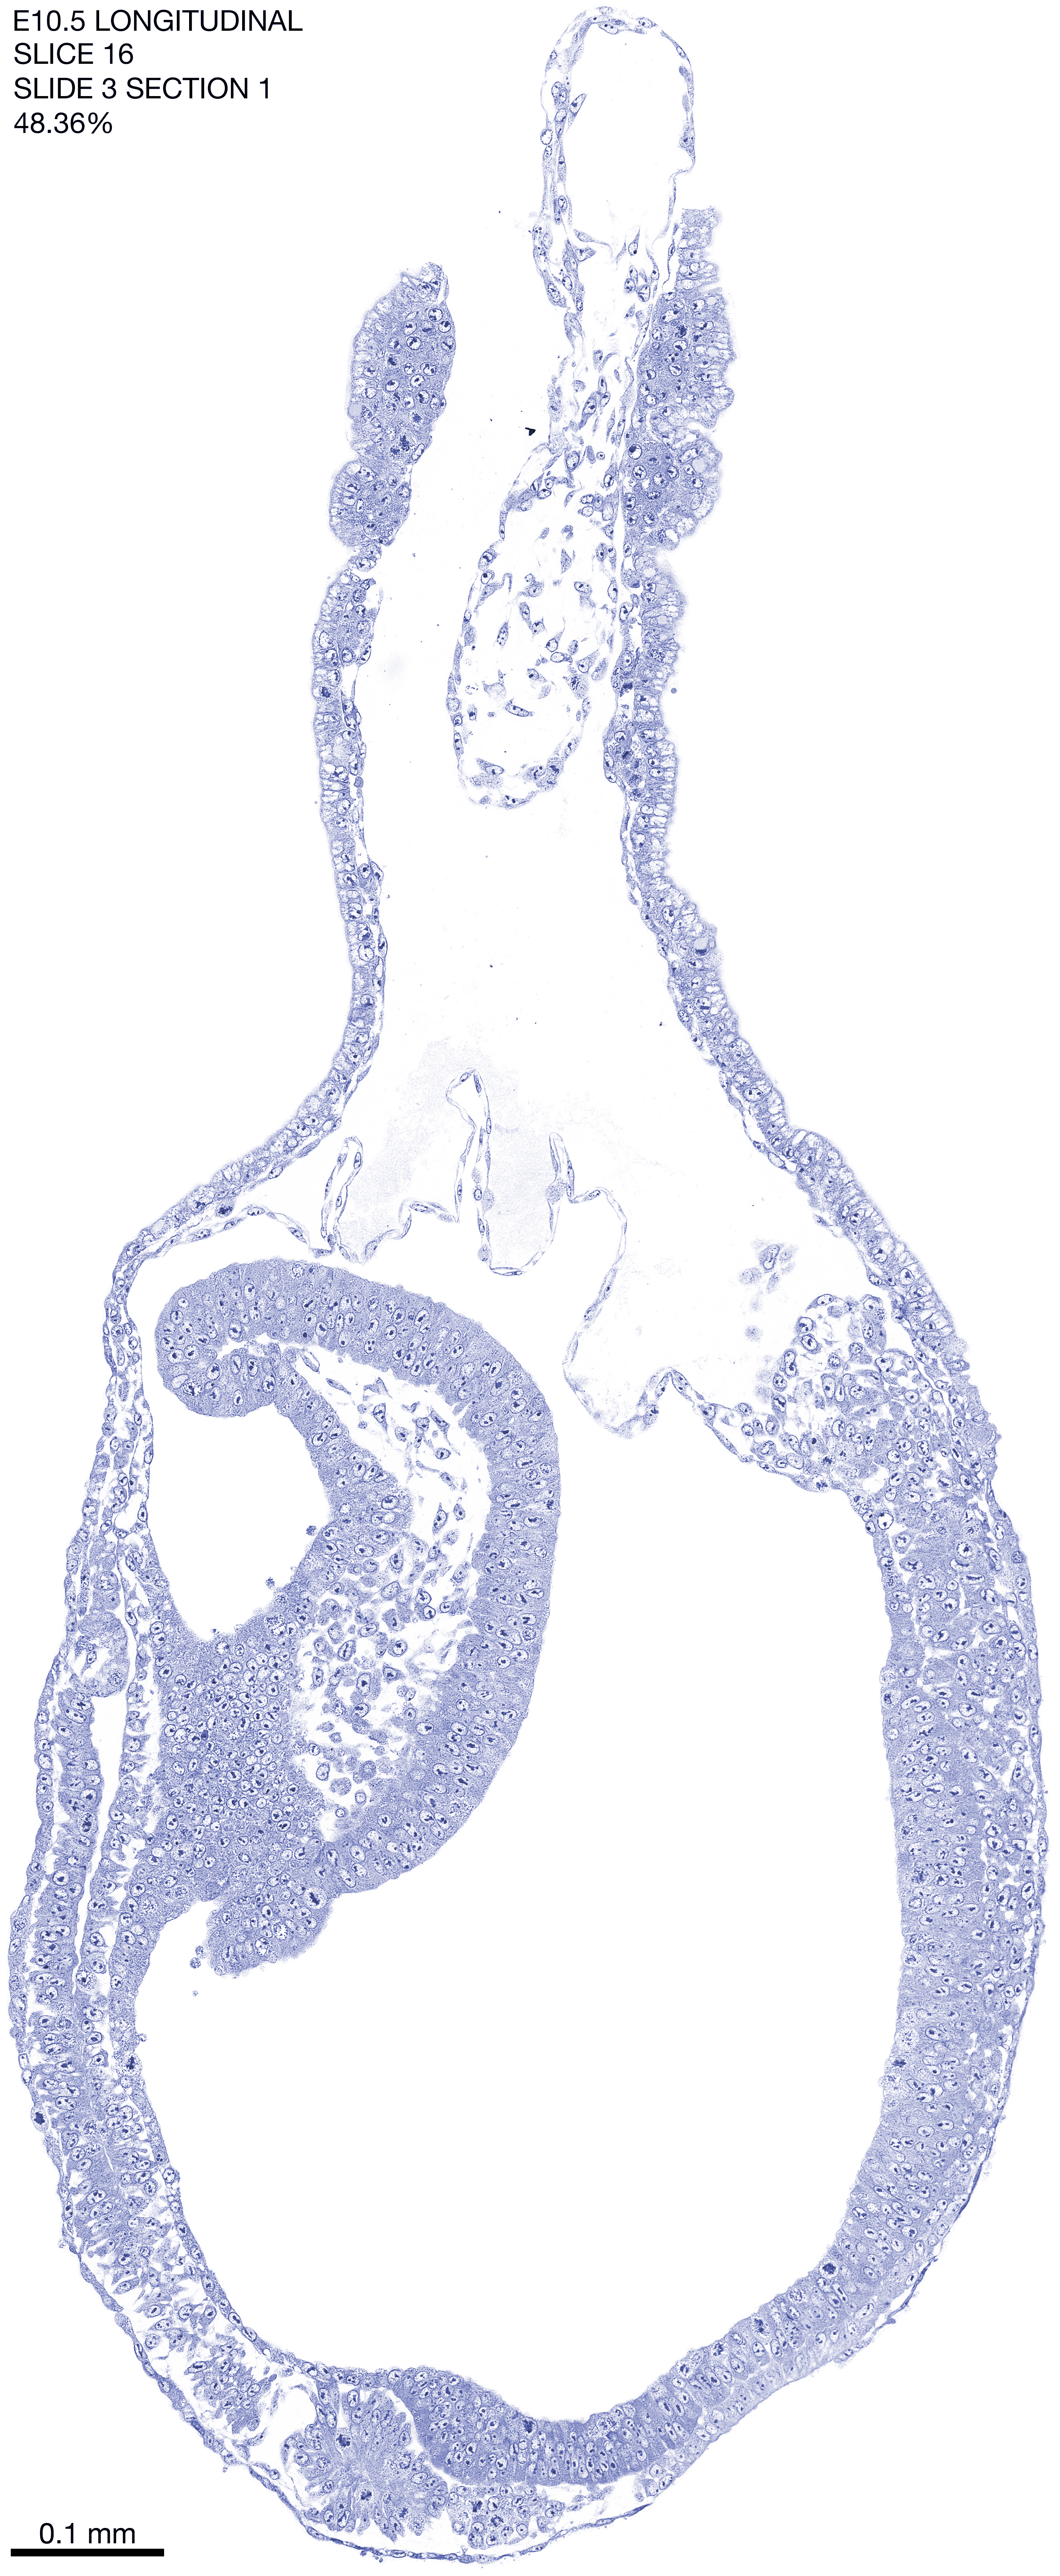

E10.5 Longitudianal Archive This page contains jpg files of ALL SLICES (each 3µm thick) that were scanned of the E10.5 longitudinally cut specimen. Download: Large | High Res Download: Large | High Res Download: Large | High Res Download: Large | High Res Download: Large | High Res Download: Large | High Res Download: Large | High Res Download: Large | High Res Download: Large | High Res Download: Large | High Res Download: Large | High Res Download: Large | High Res Download: Large | High Res Download: Large | High Res Download: Large | High Res Download: Large | High Res Download: Large | High Res Download: Large | High Res Download: Large | High Res Download: Large | High Res Download: Large | High Res Download: Large | High Res Download: Large | High Res Download: Large | High Res Download: Large | High Res Download: Large | High Res Download: Large | High Res Download: Large | High Res Download: Large | High Res Download: Large | High Res Download: Large | High Res Download: Large | High Res Download: Large | High Res Download: Large | High Res Download: Large | High Res Download: Large | High Res Download: Large | High Res Download: Large | High Res Download: Large | High Res Download: Large | High Res Download: Large | High Res Download: Large | High Res Download: Large | High Res Download: Large | High Res Download: Large | High Res Download: Large | High Res Download: Large | High Res Download: Large | High Res Download: Large | High Res Download: Large | High Res Download: Large | High Res Download: Large | High Res Download: Large | High Res Download: Large | High Res Download: Large | High Res Download: Large | High Res Download: Large | High Res Download: Large | High Res